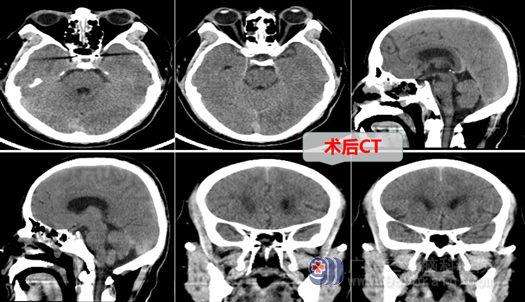

在完善相关检查后,因手术指针明确,在入院后的第3 天,外十科团队为徐大爷实施了神经内镜下经鼻蝶微创手术,短短2个小时完成手术,未发生并发症和后遗症,术后徐大爷头痛消失,恢复良好,也没有出现之前的紧张情绪,他的精神状态也一天比一天好。他现在相信了:经过鼻孔(脑部不开刀),也能切除颅内病变!